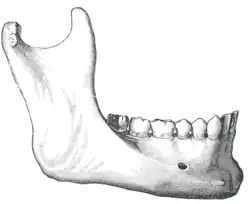

Der Alveolarkammabbau beträgt im ersten Jahr nach dem Zahnverlust etwa 0,5 mm im Oberkiefer und 1,2 mm im Unterkiefer. In den Folgejahren beträgt der Abbau 0,1 mm im Oberkiefer und 0,4 mm im Unterkiefer. Der schnellere Abbau des Unterkieferknochens resultiert unter anderem daraus, dass die Auflagefläche für eine Prothese nur etwa halb so groß ist, wie die des Oberkiefers. Im Oberkiefer liegt die Prothese auch auf dem Gaumen auf. Dadurch sind die Belastungskräfte, die auf den Unterkiefer wirken, doppelt so groß wie im Oberkiefer. Daraus folgt, dass in der Regel nach ca. 20 Jahren Prothesentragedauer der Alveolarkamm des Unterkiefers vollkommen abgebaut und der Unterkiefer flach geworden ist. Er bietet dann keinen Halt mehr für eine Totalprothese.[2]